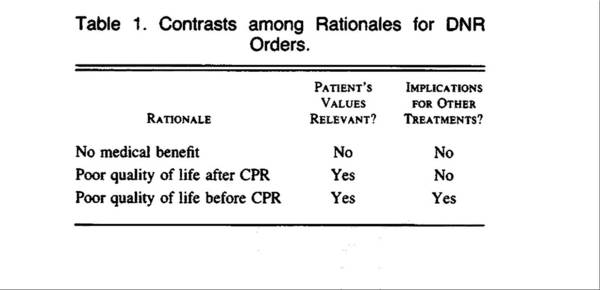

1988年1月7日

尽管"放弃抢救"(do-not-resuscitate, DNR)法令备受争议,但Tom Tomlinson和Howard Brody却提出了3点理由支持DNR。他们描述了在不同的环境下医生影响和患者及家属决策的适用性。根据作者的意见,医生在认为抢救肯定无效时,可以给出停止复苏的医嘱,但是如果以复苏前后的生活质量作为主要考虑的因素,患者及家属的价值观及医院必须纳入考虑。